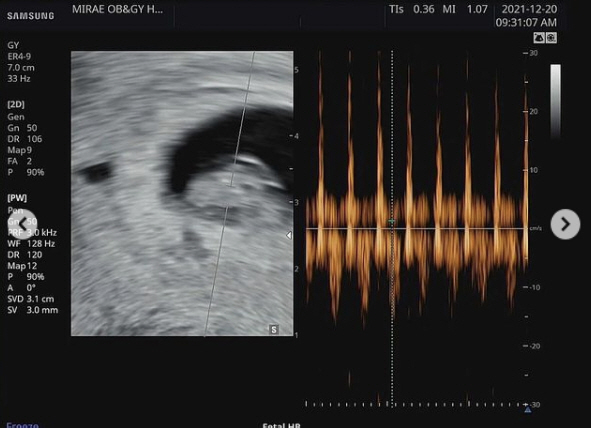

김원중 역시 인스타그램에 '아빠'를 해시태그로 달며 초음파 사진과 영화 '스타워즈' 다스베이더 가면을 쓴 채 "아임 유어 파더"라면서 곽지영의 배를 가리쳤다.

또 김원중은 곽지영의 뱃속에 있는 작지만 소중한 아기의 초음파 사진도 올렸다.